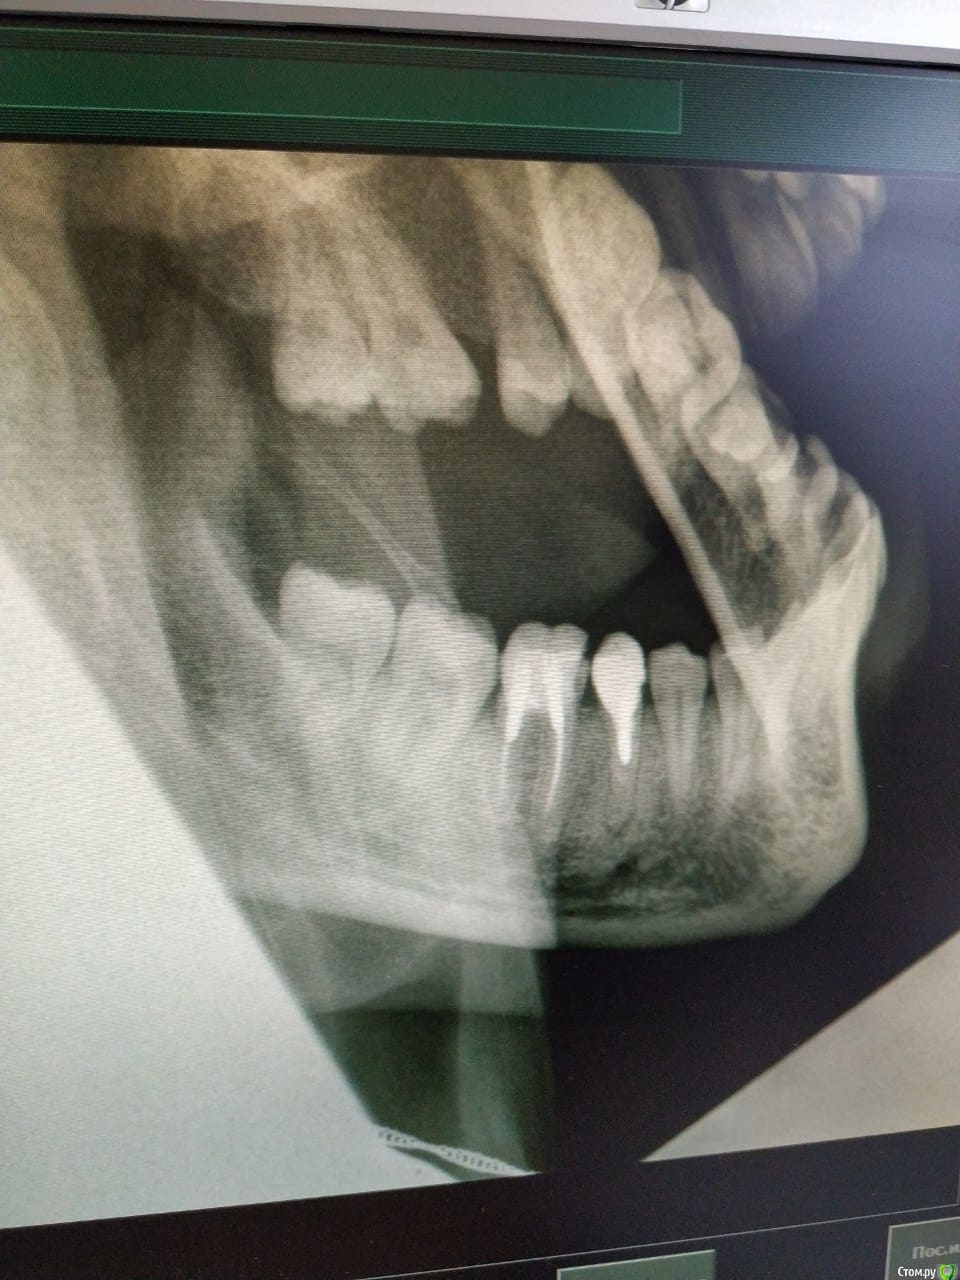

Не знаю ещё может тоже будет важно, полтора года назад немного тревожил зуб рядом 7ка, он у меня на штифте. Тогда мы тоже делали снимок (тоже прикладываю, это уже более обширный снимок). И там стоматолог мне сказал что под 7кой у меня киста, но делать ничего с тем зубом мы не стали.

post-61872-0-29428100-1605970475_thumb.jpg